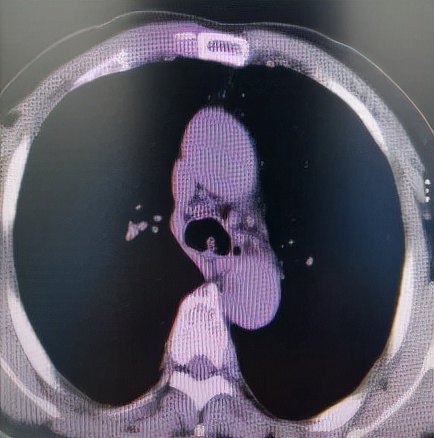

经过充分细致的各项准备工作,手术如期进行。麻醉科刘淑杰副主任医师给患者经喉罩套气管插管(8mm),在充分气道保护下插入电子支气管镜观察病变,隆突区可见菜花状新生物,表面凹凸不平,血供较丰富,新生物累及左主支气管导致管腔狭窄约80%,新生物也累及右主支气管导致管腔狭窄约60%,手术难度比预计还要高。因病变刚好位于隆突区,操作稍有不慎,很容易将隆突穿漏。术中于世寰主任熟练地交替应用各种设备,于新生物处反复施以激光蚀刻、电切刀电切、圈套器套取、二氧化碳冷冻冻取等操作,削瘤过程中的出血,应用APC充分予以止血,完美的完成了削瘤手术。术后患者很快苏醒,醒后患者的第一反馈就是呼吸顺畅多了。

削瘤前隆突区、左主、右主开口新生物